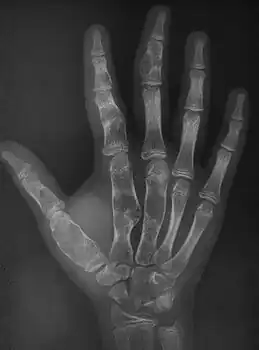

| Enchondromatosis in fingers | |

Enchondromatosis is the presence of multiple enchondromas, occurring as part of Ollier disease, Maffucci syndrome, or metachondromatosis.[3] It has a tendency to affect short tubular bones of the hands and feet, but can occur in long bones, shoulder blades and hips.[3] It presents with bone deformity, lumps, or broken bone, typically in a child.[2]

X-ray wrist: Ollier disease in child

X-ray hand:Ollier disease in child